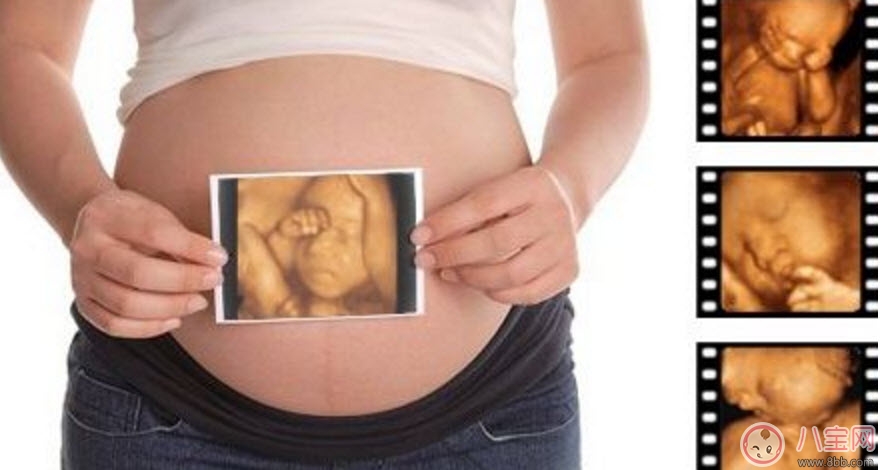

孕婦的羊水適量的話就可以做這項(xiàng)檢查。但是受胎兒體位、胎盤以及孕期不同等方面的因素影響,專家建議最佳做四維彩超的時(shí)間應(yīng)該是12-30周,這個(gè)時(shí)期就可以完全獲取到胎兒的面部以及身體等結(jié)構(gòu)的圖像。懷孕十個(gè)月的時(shí)候里最少要做3次的四維彩超,時(shí)常觀察胎兒成長(zhǎng)。

第一次檢查:選擇懷孕14周左右

選擇在懷孕4個(gè)月的時(shí)候做四維彩超檢查。在這個(gè)檢查過(guò)程中,可以觀察到胎兒的頭、體、以及四肢的整體圖像,觀察時(shí),醫(yī)生也會(huì)特別注意胎兒的整體活動(dòng)是否協(xié)調(diào)。協(xié)調(diào)的話表示胎兒生長(zhǎng)的很健康,當(dāng)然不協(xié)調(diào)的話也是可以接受治療改善的,這個(gè)時(shí)候還有時(shí)間。

第二次檢查:選擇懷孕22周左右

孕婦在懷孕5個(gè)多月的時(shí)候做四維彩超檢查。在觀察時(shí),可以明顯的看到胎兒要比上次觀察的要大,而且在同一幅圖像上還不能完全地顯示出胎兒的全部結(jié)構(gòu)??梢酝ㄟ^(guò)局部的觀察胎兒是否健全,有沒(méi)有一些其他癥狀的出現(xiàn)。如果真的這樣,胎兒很大的可能會(huì)是畸形生長(zhǎng)的、發(fā)育明顯不健康。

第三次檢查:懷孕28周左右

懷孕7個(gè)月左右也是做四維彩超檢查的好時(shí)機(jī)。這個(gè)時(shí)期的胎兒的皮下脂肪、面部表情都會(huì)比較飽滿、清晰。同時(shí)還可以看到胎兒在母體中的形體動(dòng)作以及面部表情。這個(gè)階段的檢查對(duì)于胎兒的發(fā)育是否正??梢愿用鞔_。這對(duì)懷孕晚期的胎兒健康尤其重要,所以必須好好做詳細(xì)的檢查。